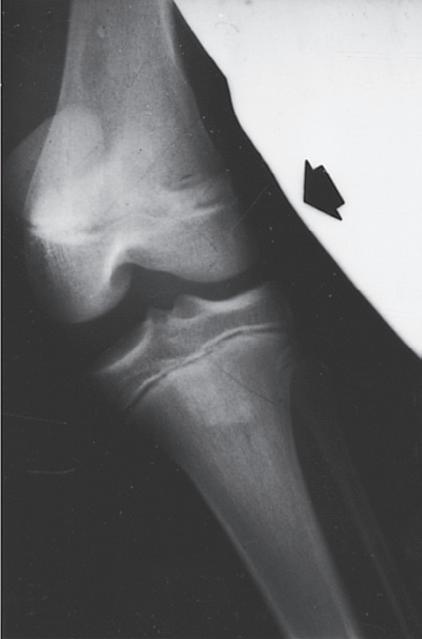

ANATOMIC DIFFERENCES OF PEDIATRIC BONES

As the skeleton of a child grows, it develops from a relatively elastic and rubbery type of biomechanical material to the more rigid structure of an adult skeleton. Because of the amount of radiolucent cartilaginous material in pediatric bone, comparison films are sometimes necessary to determine whether a radiograph is abnormal, and this lack of clarity in the radiograph can make diagnosis of fractures difficult. The types of injuries may also be different in children; for example, ligamentous injuries and dislocations are rare. Injuries around the knee frequently lead to ligamentous and meniscal injuries in adults. In children, the distal femoral or proximal tibial physis is more likely to be injured because it is the weak link (Fig. 1.7). Previously, stress radiographs were recommended, but these are usually unnecessary because the diagnosis can be made by a complete history and physical examination and confirmed at follow-up when radiographs demonstrate a widened physis consistent with a healing growth plate injury. Ligamentous injuries in skeletally immature children are uncommon, but they do occur and become more frequent in adolescence as

Fig. 1.7 Stress films illustrating injuries to the proximal tibial physis (A), the medial collateral ligament (B), and the distal femoral physis (C) in skeletally immature children. Stress films are no longer recommended. The diagnosis of a nondisplaced Salter I physeal fracture is made based on local tenderness and swelling over the physis.